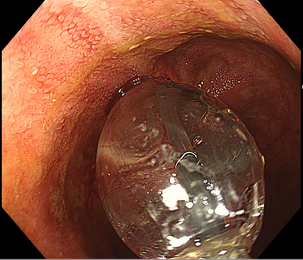

PEG(内視鏡下胃瘻造設術)

内視鏡を用いて胃瘻造設(胃に穴をあけてチューブやボタン挿入する)を行います。

何らかの病気が原因で経口摂取ができない方や、食べてもむせ込んで肺炎などを起こしやすい方が対象となります。

当院では、他医療機関から紹介の胃瘻造設や施設入所中の方の胃瘻交換も積極的に行っておりますのでお気軽にご相談ください。